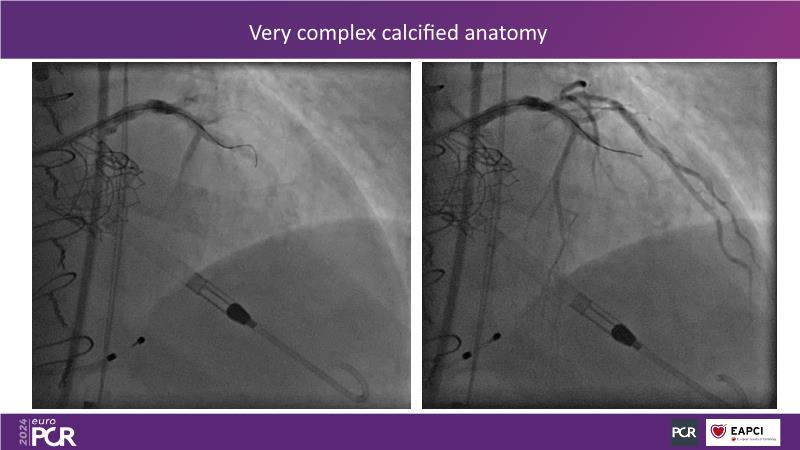

This session is essential for those looking to analyze and discuss the findings of the DanGer shock randomized trial, explore the latest evidence in the ACS field such as Horizon, and implement evidence-based practices in peri-procedural planning, execution, drug administration, and weaning strategies to optimize outcomes in acute myocardial infarction complicated by cardiogenic shock, since the session presents the latest data on ECLS and Impella, compares both in shock management, and offers insights on improving survival rates in shock patients, including the latest data on revascularization completeness with percutaneous ventricular assist devices versus IABP.